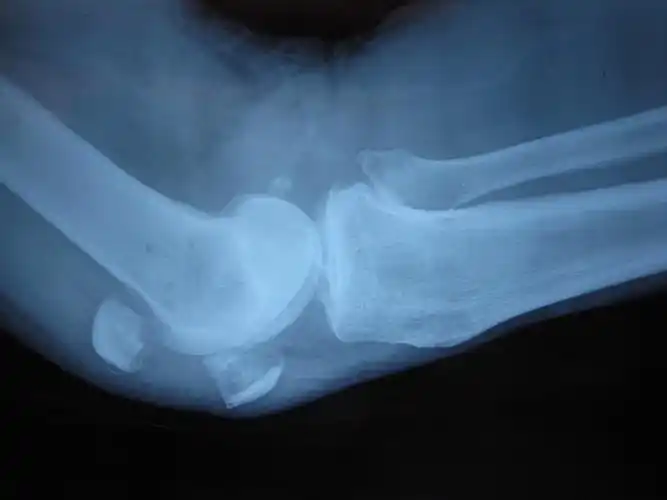

膝,x光,髌骨,射线成像,腿骨

髌骨骨折